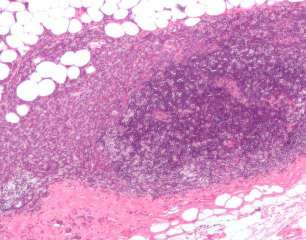

Многие виды рака вызваны рецепторами, которые способствуют росту опухоли. Но рецепторы, управляющие некоторыми типами рака, такими как TНРГ, до сих пор остаются неуловимыми для ученых. В текущем исследовании ученые из Baylor обнаружили пару рецепторов, которые способствуют этой смертельной болезни. Терапия, ингибирующая эти рецепторы в комбинации, может резко сокращать TНРГ, включая те раковые опухоли, которые устойчивы к стандартной химиотерапии.

Ранее эта исследовательская группа обнаружила ген под названием PTPN12, который предотвращает появление TНРГ. PTPN12 часто инактивируется у пациентов с TНРГ, что приводит к развитию рака. В текущем исследовании ученые обнаружили, как PTPN12 работает, чтобы предотвратить рак, отключив по меньшей мере два рецептора, способствующих его развитию. Когда PTPN12 инактивируется, эти рецепторы застревают в положении «на месте» и приводят к росту опухоли. Этот вывод заставил исследователей проверить идею, что ингибирование обоих этих ключевых рецепторов в комбинации может убить TНРГ.